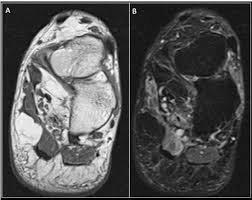

A magnetic resonance imaging (mri) was performed on a normal subject;

Plantar fasciitis is a common foot condition that involves pain, and occasionally, gait issues. It results in pain in the heel and bottom of the foot that is usually most severe with the first steps of the day or following a period of rest. Other diagnostic tests, such as magnetic resonance imaging (mri), may be done if doctors suspect the person's fascia is torn. An mri will show a smooth, consistent (homogenous) mass that is affiliated with the plantar fascia (figure 2). Stretching the calf muscles and foot often accelerates healing. To describe changes in activation of the intrinsic plantar foot muscles after 4 exercises as measured with t2 magnetic resonance imaging (mri). Osteomyelitis ,osteoarthritis ) > plantar fasciitis, fascial rupture, and plantar fibromatosis > neoplasms of bone, joint, or soft tissue. Indications for foot mri scan. A magnetic resonance imaging (mri) was performed on a normal subject; This weakness can cause slight. Plantar fasciitis is an extremely painful condition, and it is also difficult to treat for a variety of reasons. Learn vocabulary, terms and more with flashcards, games and other study tools. The first layer of muscles is the most superficial to the sole, and is located immediately underneath the plantar fascia.

Ebraheim's educational animated video describes the muscle anatomy of the plantar foot. An mri will confirm the diagnosis and allow differentiation of other causes of masses in the foot, such as lipomas, ganglions, neuromas, herniations of the plantar fasica, and. They are considered voluntary muscles. A mri scan is shown in figure 84. Indications for foot mri scan. To describe changes in activation of the intrinsic plantar foot muscles after 4 exercises as measured with t2 magnetic resonance imaging (mri). ► shoulder ► elbow ► wrist ► finger ► thumb. Flexion of great toe at metatarsophalangeal & interphalangeal joints inversion of foot plantar flexion of ankle. Start studying plantar foot muscles. Edited by brent brookbush dpt, pt, ms, pes, ces, cscs, acsm h/fs. Top suggestions for plantar foot muscles mri. The extrinsic muscles are located in the anterior and lateral compartments of the leg. Most superficial of all the layers.

They are considered voluntary muscles. Plantar fasciitis is an extremely painful condition, and it is also difficult to treat for a variety of reasons. Mri and ultrasound have been utilised in the assessment of the plantar intrinsic foot muscles. Use of mri for volume estimation of tibialis posterior and plantar intrinsic foot muscles in healthy and chronic plantar fasciitis limbs. Other diagnostic tests, such as magnetic resonance imaging (mri), may be done if doctors suspect the person's fascia is torn. Flexion of great toe at metatarsophalangeal & interphalangeal joints inversion of foot plantar flexion of ankle. They are generally divided into two sets: Plantar flexion of the foot is the opposite movement of the dorsiflexion otherwise known as pointing your toes down. Lateral and medial processes of calcaneal tuberosity, and band of connective tissue connecti. Plantar fasciitis is a disorder of the connective tissue which supports the arch of the foot. Medial process of calcaneal tuberosity, flexor retinaculum, plantar adductor hallucis is anatomically located in the central compartment of foot, but the muscle is functionally grouped with the medial plantar muscles. Key facts about the medial plantar muscles. 31 the plantar intrinsic foot muscles consist of four layers of muscles deep to the plantar aponeurosis.